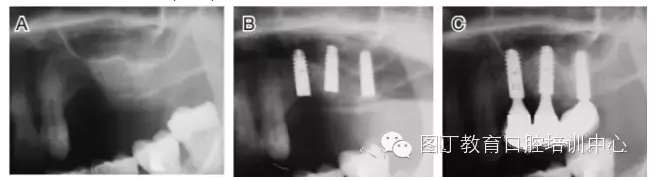

病例3 有骨間隔(圖5)

圖5